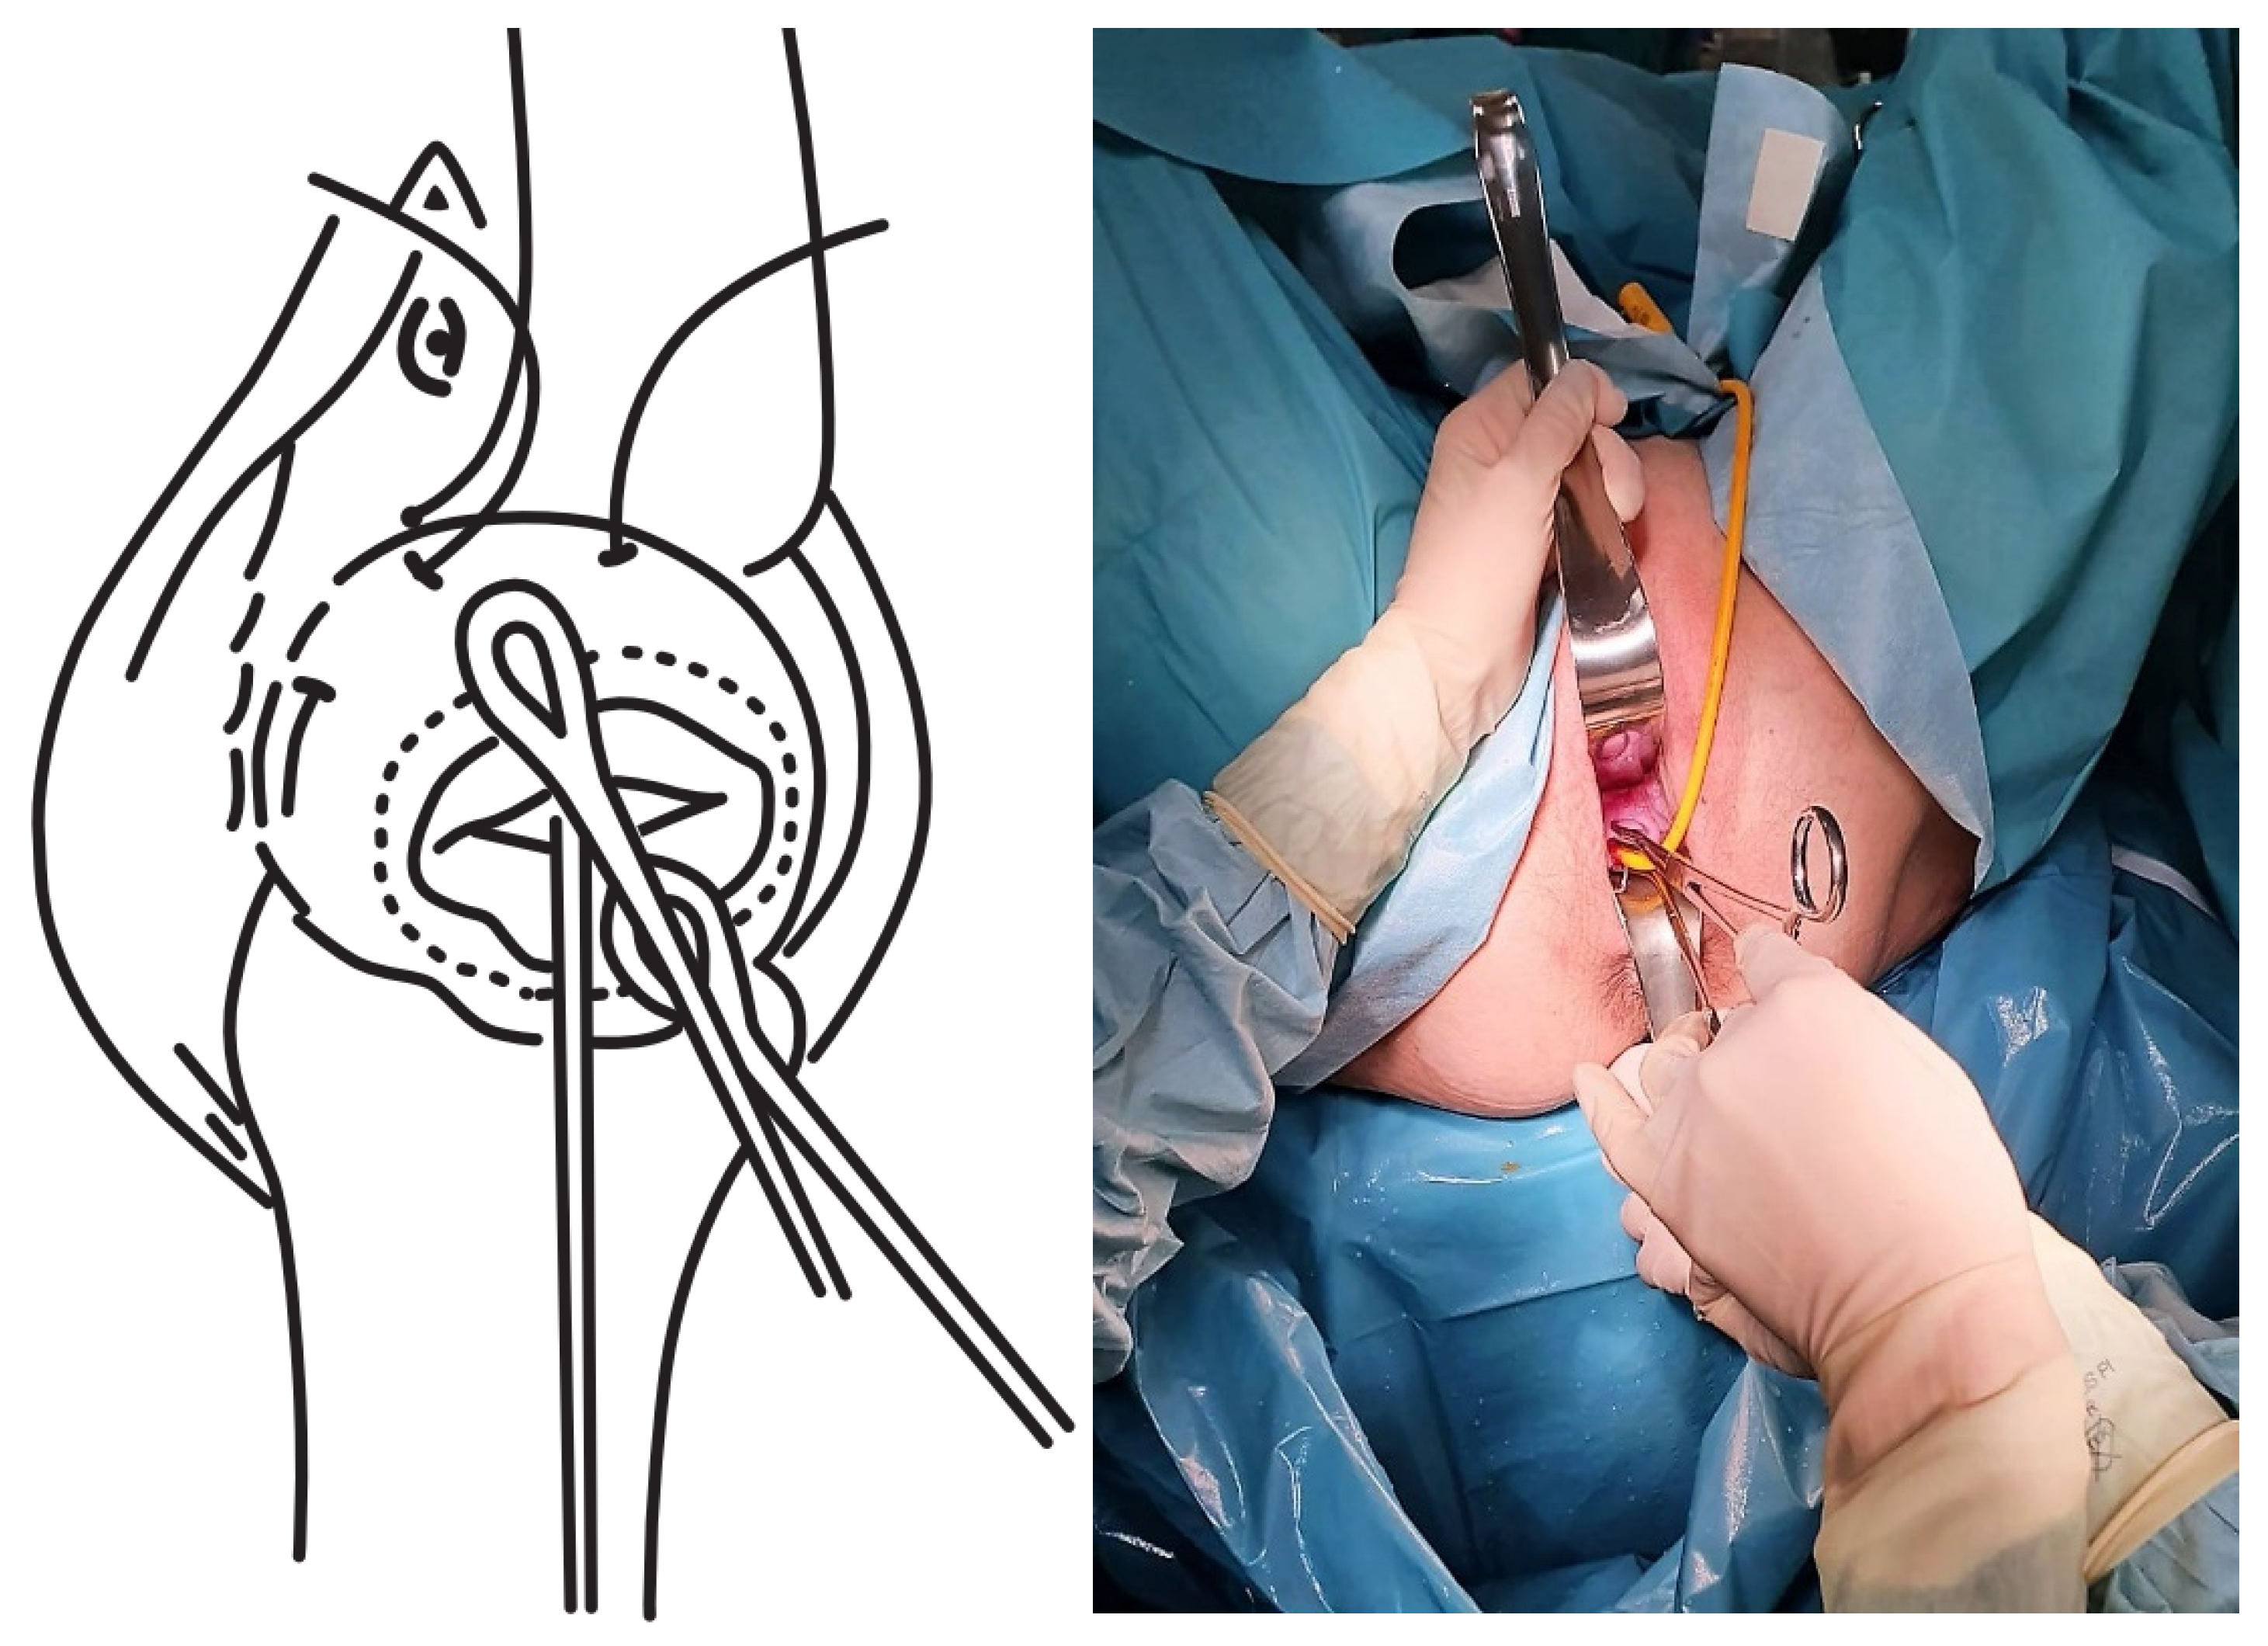

- The first cerclage was performed using Prolene 1. A purse-string suture was placed as cranially as possible and as close as possible to the level of the internal cervical os, with care taken not to damage the bladder. The suture was superficially applied without going too deep into the cervical stroma since this step aims to keep the bag reduced once the Foley catheter had been removed and to leave a segment of the cervix free on which to perform a second cerclage such that conglutination is guaranteed (Figure 2).